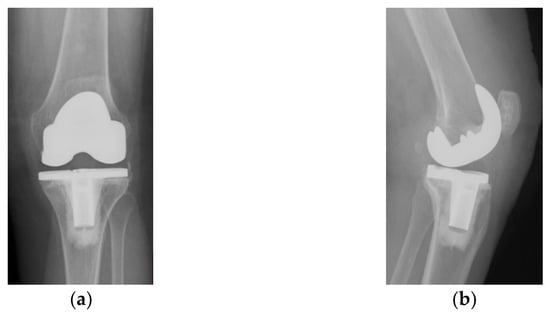

Four years ago, the patient was diagnosed with Ahlback stage IV gonarthrosis and underwent a simultaneous bilateral TKA surgery in another orthopedic clinic. Two NexGen cemented total prostheses were then implanted, with patellar resurfacing performed only on the right side, due to anesthetic complications which required a drastic shortening of the operating time, thus preventing the surgical team from performing resurfacing on the contralateral patella. Although postoperative radiological images showed a slight implantation error in the femoral component on the right side, extensive anterior resection with posterior rotation of the femoral component, the clinical outcome was satisfactory (Figure 1).

Figure 1.

Right knee, initial after surgery radiological image: (a) lateral view, extensive anterior resection, femoral posterior rotation, femoral component axis intersecting diaphyseal axis at a 15.4° angle with (1) marking the femoral diaphyseal axis and (2) marking femoral component rotation axis; (b) coronal view.

On the other hand, on the left side, where patellar resurfacing was not performed, although the radiological images show a satisfactory implantation of the prosthesis with correct alignment of the tibial and femoral components, but with slight subluxation of the patella, the clinical evolution was unsatisfactory (Figure 2). Shortly after operation, 3–4 weeks, the patient experienced discomfort, pain and swelling of the left knee.

Figure 2.

Initial radiological aspect of the left knee, right after surgery: (a) lateral view, femoral component axis parallel with femoral diaphyseal axis; (b) coronal view, slight lateral patellar subluxation (arrow) compared to femoral axis with (1) marking the femoral trochlear axis, (2) the patellar axis, and (3) patella must be centered in the femoral trochlea.